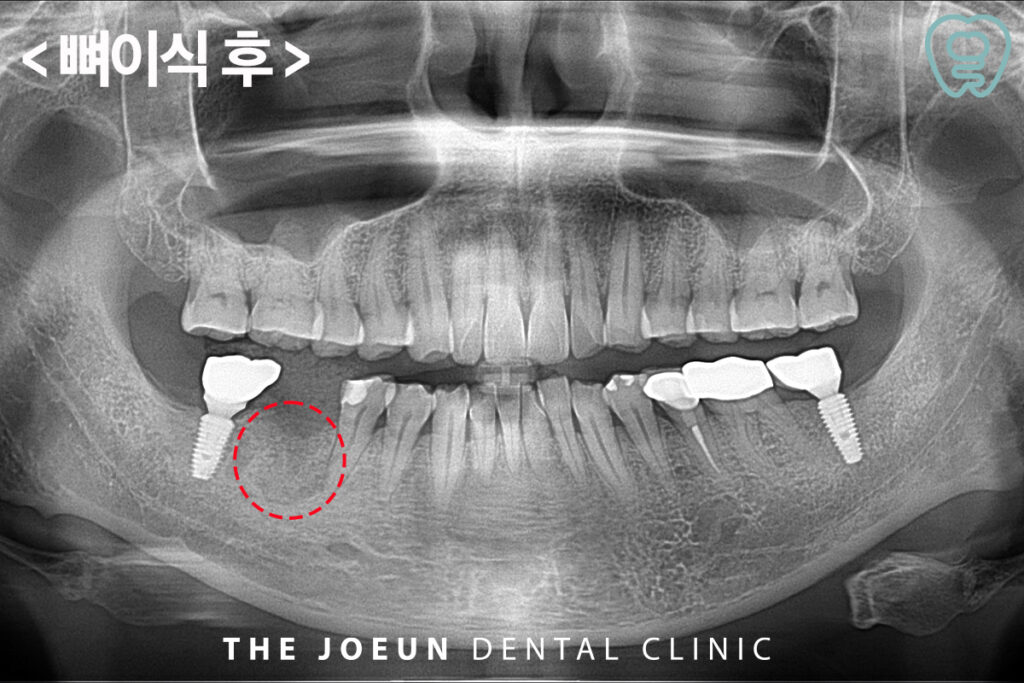

먼저 염증이 심한 치아를 발치하고 뼈이식을 진행하였습니다.

뼈이식 후에는 일정 기간동안 골조직이 자리 잡는 과정을 거쳐야 하는데요,. 일반적으로 뼈이식 후 3~6개월 동안 뼈가 단단하게 형성되는 시간을 가지며 이후 임플란트 식립이 가능해집니다. 이 과정에서 환자의 구강 건강 상태, 생활 습관, 뼈이식 재료 등에 따라 치유 속도가 달라질 수 있습니다. 특히 흡연자의 경우 혈류 공급이 원활하지 않아 뼈 형성이 지연될 수 있으므로 주의가 필요합니다.